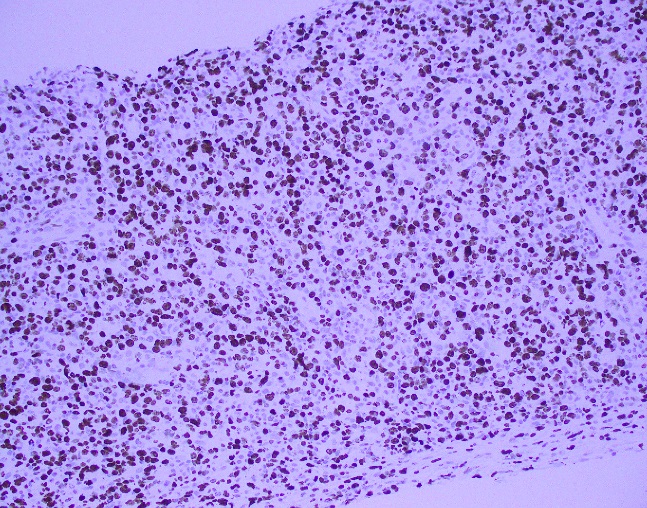

Histologically, the tumor consisted of spindle cells arranged in a fascicular pattern with intermittent whorled areas. The cells contained pleomorphic, hyperchromatic nuclei and intervening myxoid hypocellular areas. Mitotic figures were observed with sparse areas of necrosis and hemorrhage. S-100 was ordered on the prior biopsy of the mass, which was weakly positive. Based on these findings, the specimen was signed out as a malignant peripheral nerve sheath tumor.

Grossly, MPNST will present as a large, poorly defined, fleshy tumor that runs along a nerve and involves adjacent soft tissue. Often, these tumors will have areas of hemorrhage or necrosis and can track along the length of a nerve. Histologically, the tumors are composed of monomorphic spindle cells arranged in fascicles, palisades and whorls, with compact comma-shaped, wavy or buckled hyperchromatic nuclei with alternating hypocellular foci. (Image 3 and 4). Mitotic figures and necrosis are common, and although S-100 is considered the best marker for MPNST, there is a lack of specificity and sensitivity for immunohistochemical markers. Due to the lack of immunohistochemical markers and molecular findings, as well as the variability associated with the cells, it has traditionally been difficult to diagnose MPNST. The differential diagnosis includes fibrosarcoma, monophasic synovial sarcoma, desmoplastic melanoma, and pleomorphic liposarcoma. Goldblum et al put forth the idea that a diagnosis of MPNST can be made if the tumor falls into any one of the following three categories: